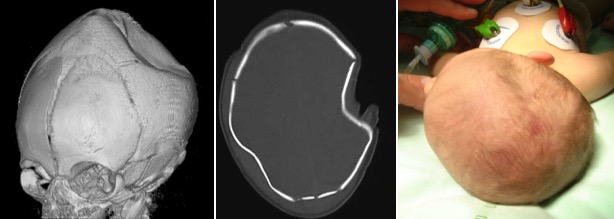

synonymes : depressed fracture ; ping-pong fracture

la voûte crânienne du nouveau-né est douée d’une certaine élasticité. en cas de compression appuyée, notamment au cours de l’accouchement, elle peut inverser sa courbure. L’embarrure nécessite souvent un correction chirurgicale qui doit être précoce, elle ne laisse pas de séquelles. il s’agit donc d’une condition tout à fait bénigne.

il est évident à l’inspection. il s’agit le plus souvent de la voûte pariétale, rarement de la voûte frontale.

le scanner permet de s’assurer de l’absence de lésion traumatique intracrânienne.